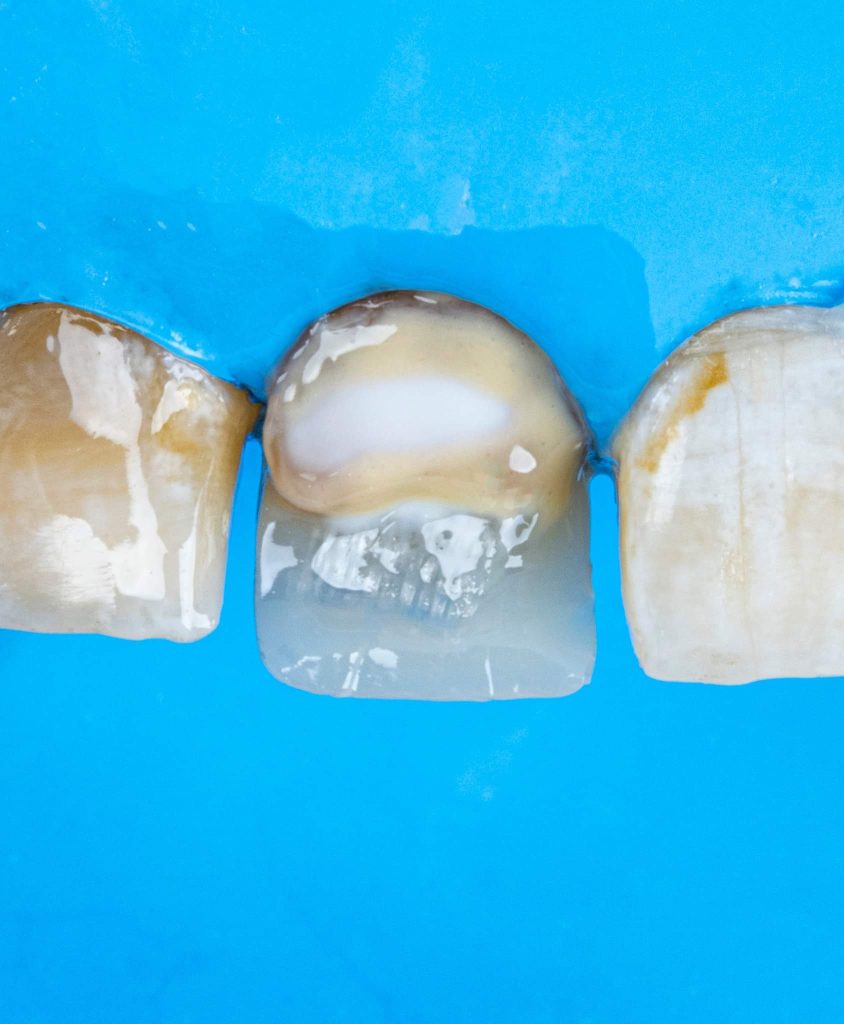

1.Masking the discoloration: This is where one or several shades of composite resin are used to camouflage the underlying darkened tooth shade. For severe discolorations, a resin-based opaque layer placed over the discolored areas of tooth may be required. This is then covered with dentine and enamel shades to match the adjacent teeth.

This is a case of discolored right central incisor for a 21 years-old-male patient. He had a history of previous trauma 2 years ago to his tooth and fracture, that was managed with a composite restoration. After clinical examination and x-ray imaging, the tooth was non-vital with periapical lesion.

After discussing the treatment options with the patient, he chose the direct composite veneer. The treatment included endodontic treatment, internal bleaching, direct composite veneer for the right central, and aesthetic reshaping for the laterals and left incisor also by composite restoration. The case completed in 2 sessions.